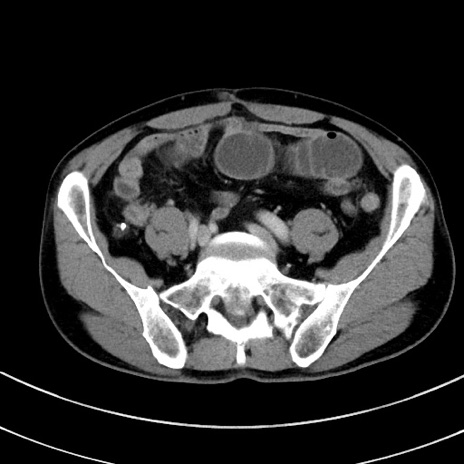

症例8(横断像)

【症例】 60歳代男性

【主訴】 黒色吐物

【現病歴】 4日前から嘔気自覚、2日前の朝食後にも嘔気あり、自分で手で嘔吐反射起こし嘔吐したところ血が混ざっていたため受診。

【既往歴】 5年前汎発性腹膜炎を伴う急性虫垂炎で手術、高血圧、前立腺肥大症、高脂血症

【身体所見】 腹部正中に手術癩痕あり 腹部平坦・軟圧痛なし膨満感あり

【データ】WBC 8400、CRP 4.54